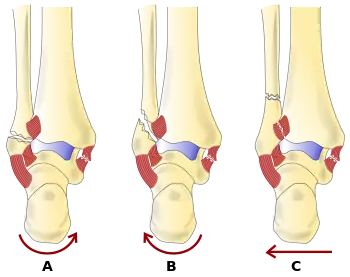

Danis-Weber classification (type A, B and C)

There are several classification schemes for ankle fractures. Out of the following, the Lauge-Hansen and Danis-Weber classification systems are most commonly used.[8]

• The Lauge-Hansen classification categorizes fractures based on the mechanism of the injury as it relates to the position of the foot and the deforming force (the most common type is supination-external rotation)

• The Danis-Weber classification categorizes ankle fractures by the level of the fracture of the distal fibula (type A = below the syndesmotic ligament, type B = at its level, type C = above the ligament), with use in assessing injury to the syndesmosis and the interosseous membrane